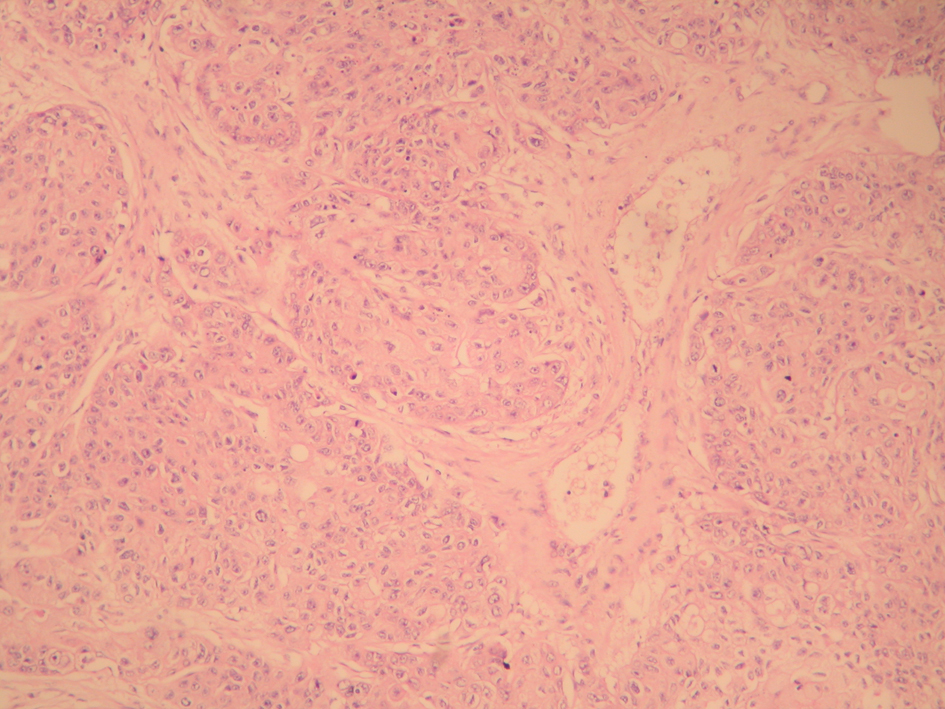

A 48-year-old male patient presented to the urology clinic for painless swelling of his right testis that has been going on approximately for two months. The patient had 60 pack/years of smoking history, and considering presence of a primary testicular tumor, he was scheduled for a surgery by the urology department. His pre-operative B-HCG and AFP levels were assessed, and found within acceptable limits, and he underwent orchiectomy. The immunohistochemical staining performed for the patient, who had a manifestation consistent with squamous cell cancer during the pathological assessment showed focal CK19 and keratin positivity as well as PLAP, AFP, CD30, CK5/6, HMWCK, TTF-1, HMB45 AND Melanin A negativity (Fig. 1 and 2). After the histological subtype was identified as squamous cell carcinoma, PET/CT imaging that was performed to detect the primary disease revealed a 3.5 cm malignant tumor in the right lung with an SUVmax of 9, metastatic nodules in bilateral lungs with an SUVmax of 2.6, and bone metastases in the right supraclavicular, upper right paratracheal, aorticopulmonary, subcarineal and left hiler lymph nodes with an SUVmax of 13, in the right surrenal gland with an SUVmax of 9.4, and in the lumbar vertebrae and left iliac bone with an SUVmax of 4 (Fig. 3). Considering squamous cell carcinoma of the lung as a primary focus, a palliative treatment was initiated with Gemzar (1,000 mg/m2, on day 1 and day 8, every 3 weeks), Cisplatin (75 mg/m2, on day 1, every 3 weeks), and zoledronic acid (4 mg/day, every 3 weeks).

![]() Click for large image | Figure 1. Malignant epithelial tumor infiltration within the interstisium of the testicular parenchima (H&E stain, × 100). |